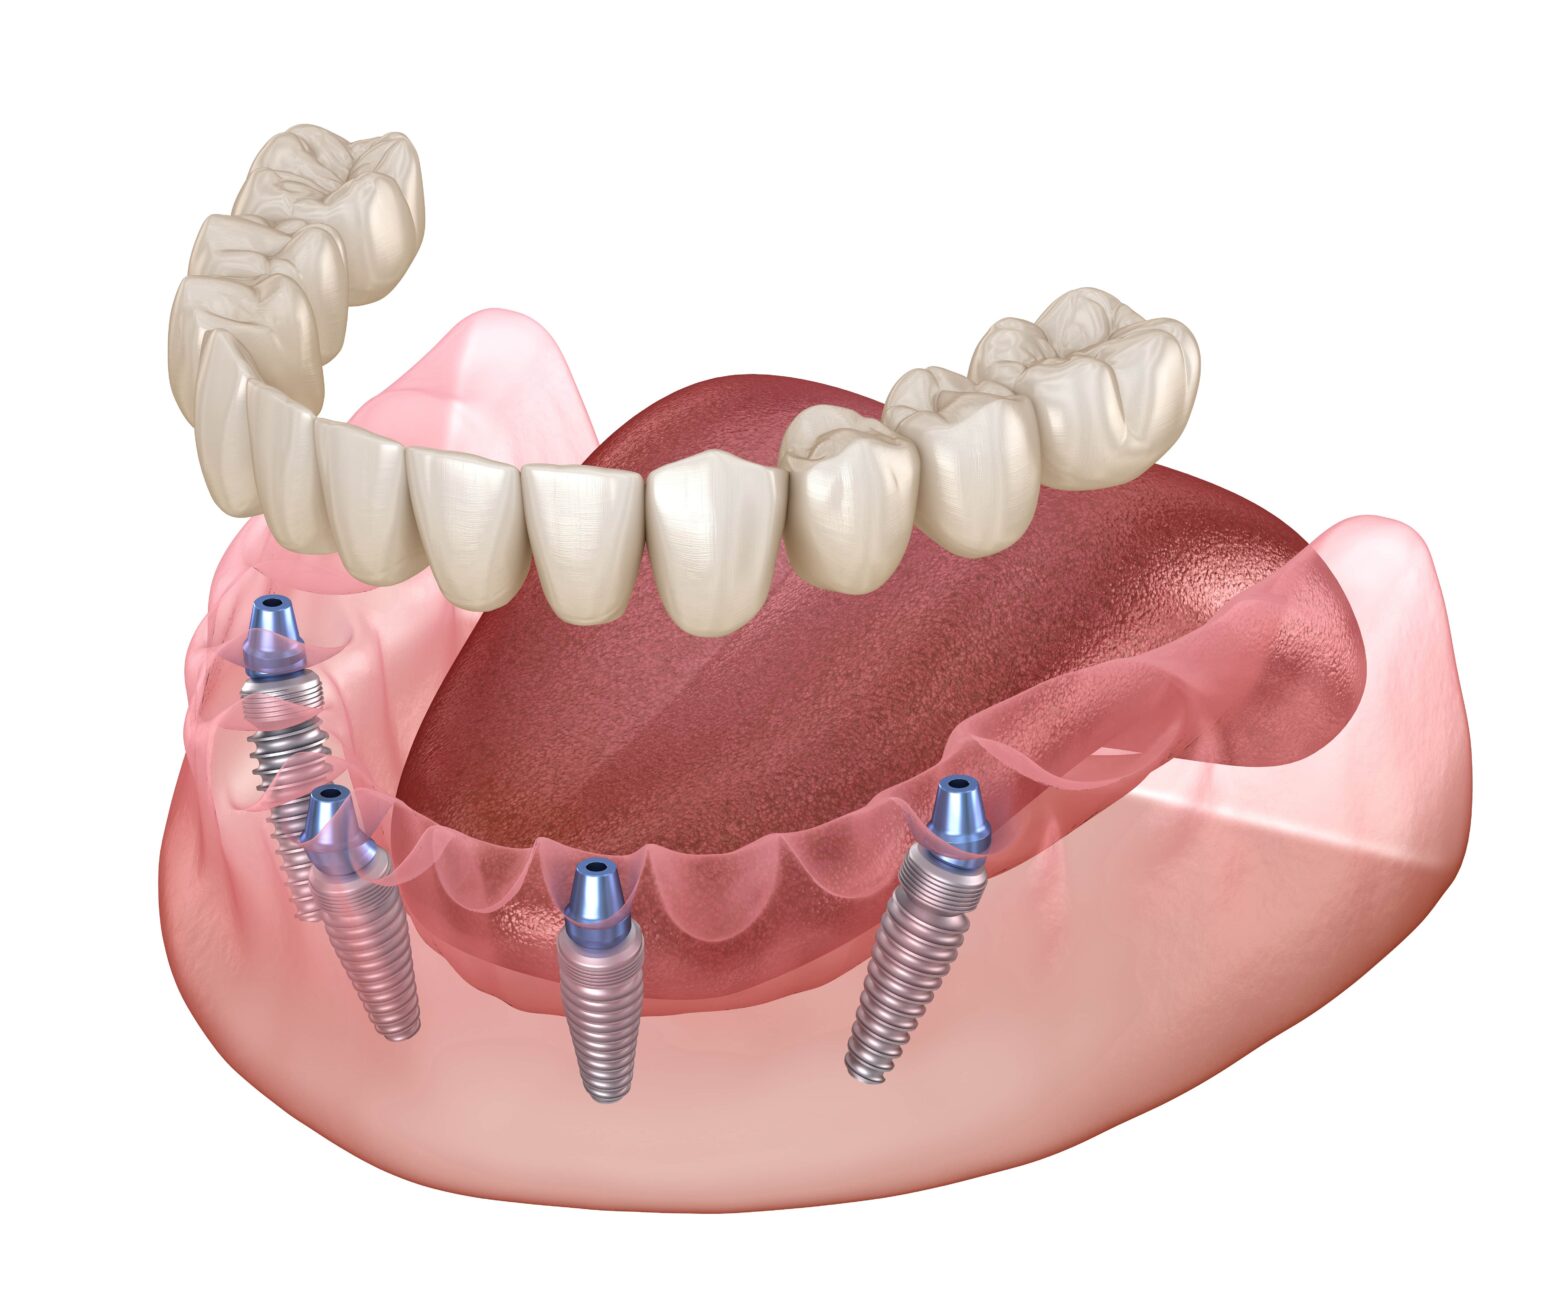

Implant-Supported Dentures: The Best of Both Worlds

This innovative solution combines the stability of implants with the full-arch replacement of dentures. You can enjoy enhanced stability and confidence by securing dentures to strategically placed implants without worrying about slippage. This option proves particularly beneficial for lower dentures, which traditionally have less stability.